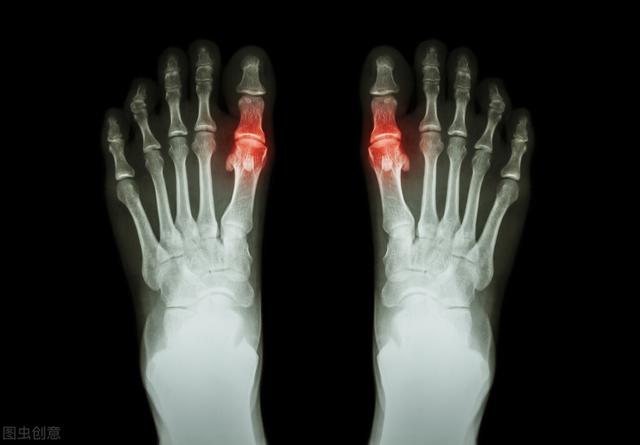

痛風かどうかを判断する方法は、主に関節による。53%から70%の患者の発症当初は、第一趾の関節(足痛風と呼ばれる)が赤く腫れ、熱く痛み、通常は多発し、一部は複数の関節として現れることもある。固定性、非対称性で、次第に足首、膝、手首、肘などの大きな関節に浸潤することもある。

痛風の急性発作では、しばしば罹患した関節(最も一般的なのは母趾と足背)に著しい局所の発赤、腫脹、熱感、疼痛、機能障害がみられる。

- 急性痛風の症状には、痛み以外に、通常、発作部位の発赤、腫脹、局所の温感、著しい圧迫痛が含まれる。第1中足趾節関節に急性痛風発作が起こると、足が腫れて靴が履けなくなり、痛みが激しくて歩けなくなります。